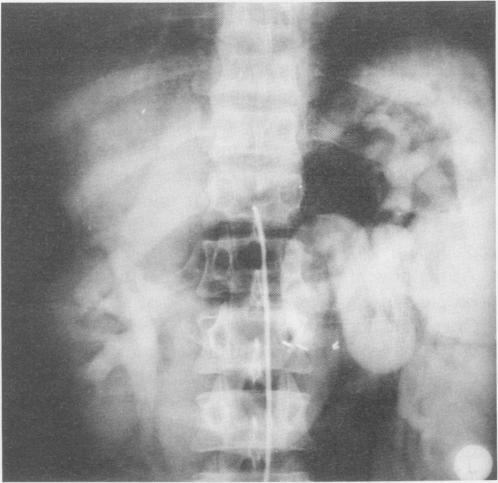

The distal splenorenal shunt (DSRS) was performed in 125 consecutive variceal bleeders. To date, no patients have been lost to follow-up (mean of 79 +/- 20 months). Liver pathology was documented in 85 patients: 45 patients had schistosomal hepatic fibrosis, 17 had nonalcoholic cirrhosis, and 23 had mixed pattern (hepatic fibrosis and cirrhosis). The preoperative data base for these three groups was matched (p greater than 0.05), with a mean follow-up of 79 +/- 20, 70 +/- 14, and 77 +/- 22 months for each population, respectively. The results showed low operative mortality (4.8%), high cumulative patency rate (94.8%) and low recurrent variceal hemorrhage (5.6%). The biochemical data showed significant increase in serum bilirubin (p less than 0.001) and aspartate transaminase (AST) (p less than 0.05) in the nonschistosomal patients. Chronic hyperbilirubinemia was found in 33% of the schistosomal group. Prograde portal perfusion was detected in 94% of the patients, with development of collaterals in 91%. The angiographic pattern of these collaterals was 50% pancreatic, 45% gastric, and 26% colosplenic. Patients with mixed liver disease had a high incidence of Grade III portal perfusion (57%) and more common pancreatic and gastric collaterals (71%). The cumulative survival for all patients was 74.1%, with hepatic cell failure being the leading cause of death (13 patients, 50% of all deaths). The schistosomal patients had a 91.6% incidence, whereas the cirrhotic and mixed groups had survival rates of 75.6% and 65.2%, respectively. Also, of a 15% total incidence of encephalopathy, 4.4% was related to the schistosomal patients, 23.5% to the cirrhotics, and 21.7% to the mixed population. Statistically, the survival rate was significantly better (p less than 0.05) and encephalopathy was significantly lower (p less than 0.05) in the schistosomal population. In conclusion, this data shows that: 1) DSRS has a high patency rate and a low variceal hemorrhage recurrence rate; 2) it maintains some degree of portal perfusion in patients with different nonalcoholic liver diseases, despite development of collaterals; and 3) the schistosomal patients have a better survival rate, with a low incidence of encephalopathy after DSRS, compared with the cirrhotic and mixed populations.